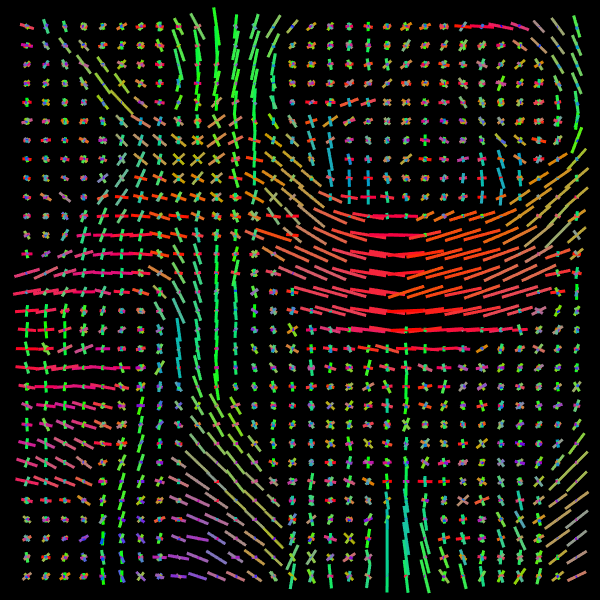

Training stage. We compare the results of the proposed Voxel (VOX) and Neighborhood (NBH) models with two of the SOTA methods which tackle the same task: Diffusion Basis Functions (NNLS) proposed by Ramirez-Manzanares et al. (2007)) and Constrained Spherical Deconvolution (CSD) proposed by Tournier et al. (2007). There are many options to compare distributions, a common comparisson procedure used in this context is to detect peaks and compute the angular error between the real peaks and the estimated ones. However, to compare modes in not a standard procedure for comparing distributions. Among them two notable options are Kullback-Leibler (KL) Divergence and the Wasserstein Distance (also know as the Earth Mover Distance, EMD). Despite its computational cost, EMD has shown to represents more precisely the distribution distance (Levina and Bickel, 2001; Aranda et al., 2011; Arjovsky et al., 2017). EMD represents the minimum cost of transforming a peak distribution into another, weighting by angle. We create a synthetic dataset with gradient table of the Stanford HARDI dataset (Rokem et al., 2015), the eigenvalues of a Diffusion Tensor model fitted to the corpus callosum region, and the SNR computed in such a data (Descoteaux et al., 2011). The estimated SNR depends on image region: most of the measures laid into [20,24]2024[20,24], so we randomly generate data selecting the SNR into [20,30]2030[20,30]. Figure 5 depicts the error for each analyzed model. The vertical axis corresponds to the angle (θ1subscript𝜃1\theta_{1}) between the first PDD and the second one. Meanwhile, the horizontal axis shows the angle between the third PDD and the plane formed by the first two PDDs. The dynamic range of the error maps shows a better performance of the proposed models. We select some predictions for a visual inspection (qualitatively comparison). For illustration purposes, we choose one between the top–101010 and one of the bottom–101010 according to its EMD values for the studied models: VOX, NBH, NNLS, and CSD. The results are presented in Figure 6. The first two columns correspond to the best predictions: the first column shows the target and the second column shows the prediction. The third and fourth columns follow the same order but for the worst predictions. Arrows illustrate the generated PDDs (ground truth). According to the α𝛼\alpha value: blue, orange, and green were used for the first, second, and third PDD, respectively.

Refer to caption

Figure 5: EMD (error) heat-maps by model predictions.